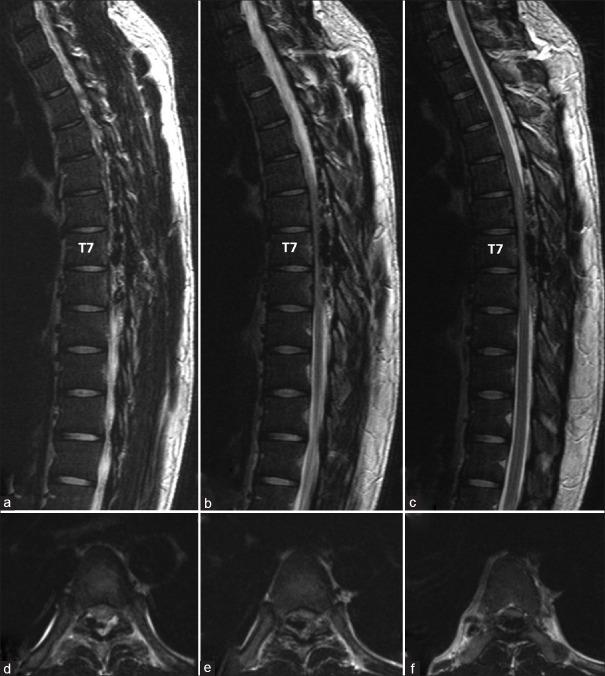

The authors describe an extremely rare case of spinal osseous epidural arteriovenous fistulas (SOEAVFs) with unique characteristic features. A 25-year-old man presented with progressive weakness and paresthesia of the lower extremities for 1 month. Magnetic resonance imaging of the thoracic spine showed an extradural dilated vascular flow void structure extending from T4 to T8 levels with abnormal hyperintense T2 signal from T6 to T8 levels. Magnetic resonance angiography and spinal angiography revealed unique features of SOEAVF supplied by multiple small arterial feeders of intercostal arteries converging into a dilated round venous sac corresponding to a bony defect of T7 lamina and spinous process. The venous drainage directly drained into prominent epidural venous plexus extending from the level of T4 to T8 without intradural venous drainage, causing severe compressive myelopathy. Transarterial embolization was performed using N-butyl cyanoacrylate through the main feeder. Subsequently, he successfully underwent laminectomy and total excision of the fistula and large epidural draining venous plexus. Histopathology confirmed spinal vascular malformations with evidence of previous embolization. He gradually improved until being ability to walk independently 3 months later. Follow-up spinal angiography confirmed complete resection of SOEAVF. The patient has remained clinically asymptomatic 5 years after operation.

作者描述了一例极为罕见的具有独特特征的脊柱骨膜外动静脉瘘(SOEAVF)。一名25岁男性出现下肢进行性无力和感觉异常1个月。胸椎磁共振成像显示硬膜外扩张的血管流空结构从T4延伸至T8水平,T6至T8水平T2信号异常高。磁共振血管造影和脊髓血管造影显示SOEAVF的独特特征,由多条肋间动脉的小动脉分支供血,汇聚成一个扩张的圆形静脉囊,对应于T7椎板和棘突的骨缺损。静脉引流直接流入从T4至T8水平延伸的突出硬膜外静脉丛,无硬膜内静脉引流,导致严重的压迫性脊髓病。通过主要供血动脉使用氰基丙烯酸正丁酯进行经动脉栓塞。随后,他成功接受了椎板切除术以及瘘管和大型硬膜外引流静脉丛的完全切除。组织病理学证实为脊柱血管畸形,有先前栓塞的证据。他逐渐好转,3个月后能够独立行走。随访脊髓血管造影证实SOEAVF已完全切除。患者术后5年一直无临床症状。